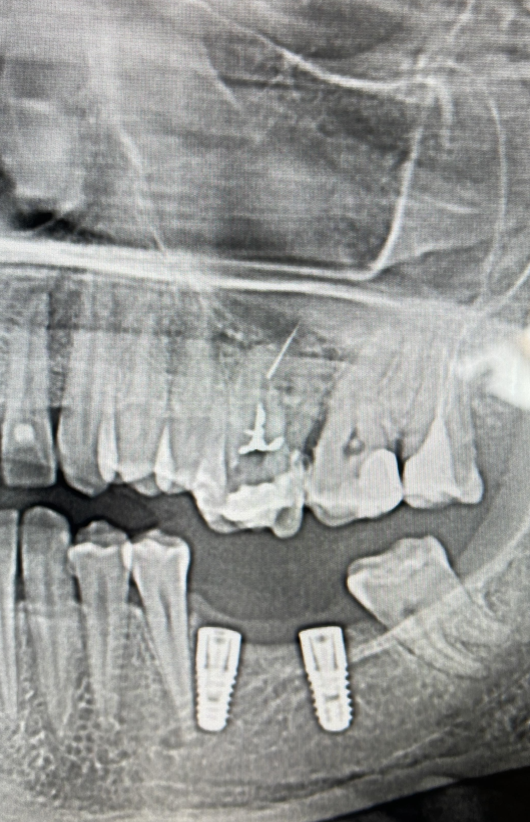

Din imagistica initiala, un OPT, putem lesne intelege ca instrumentul fracturat se afla in depasirea foramenului apical, fapt ce complica prognosticul dintelui (fig. 1).